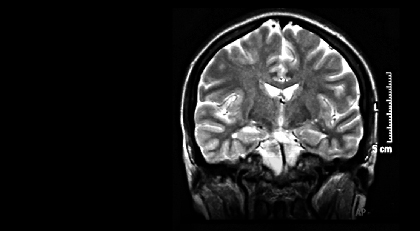

Wir bilden die Welt in unserem Kopf ab. Natürlich nicht 1 zu 1, aber in 0 und 1. Unsere Welt ist digital. Nur wesentlich komplexer als im Computer.

Wir denken im Kopf dort, wo wir wahrnehmen. Und wir erinnern dort, wo wir denken. Was auch immer uns auffällt oder länger durch den Kopf schwirrt, muss eine wesentliche Eigenschaft besitzen: Es muss uns berühren, eine Wertigkeit haben, eine Emotion, einen Nutzen. Wie auch immer man es nennen will, es hat den Wert, bedacht zu werden. Das kostet Energie.

Diese Wertigkeit, diese Emotion investiert unser Gehirn in Leitungsbahnen, in eine schnellere, effizientere Verschaltung. So werden Gefühle zu Körper verbaut. Den Bauplan dazu hat als erster Eric Kandel mit seinen Mitarbeitern auf der Ebene der Neurone entschlüsselt und dafür den Nobelpreis erhalten.

Unser Gehirn ist eine Bewertungsmaschine, die alles im Hier und Jetzt verrechnet – und im wahrsten Sinne des Wortes auf den vergangenen Erfahrungen aufbaut; auf den emotionalen Erfahrungen. Schlüsselreize werden leichter wahrgenommen, emotionale Erinnerungen leichter abgerufen. Was uns nicht bewegt, wird einfach ignoriert. Emotion ist das Geld des Gehirns. Nur wo es hinfließt, wird gebaut.